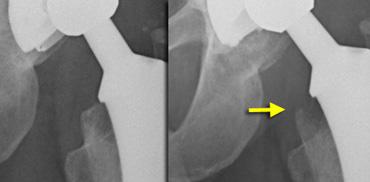

Trường hợp bên trái cho thấy sự di chuyển của chỏm acetabulum, điều này sẽ được nhận thấy rõ hơn nếu sử dụng một điểm tham chiếu (xem hình tiếp theo)

Same case as above with white marks on the tear drop figure. Migration is shown more easily. Blue arrow indicates acetabular fracture.

Nếu chúng ta quan sát các phim X-quang tương tự và sử dụng hình giọt nước mắt làm mốc giải phẫu, sự di trú sẽ trở nên rõ ràng hơn.

Sự di trú của chỏm lên phía đầu đã dẫn đến gãy thành ổ cối (mũi tên xanh).

Sự di chuyển của các thành phần ổ cối là không bao giờ được chấp nhận.

Nó được nhận thấy như sự di chuyển lên trên hoặc nghiêng của chỏm (hình)